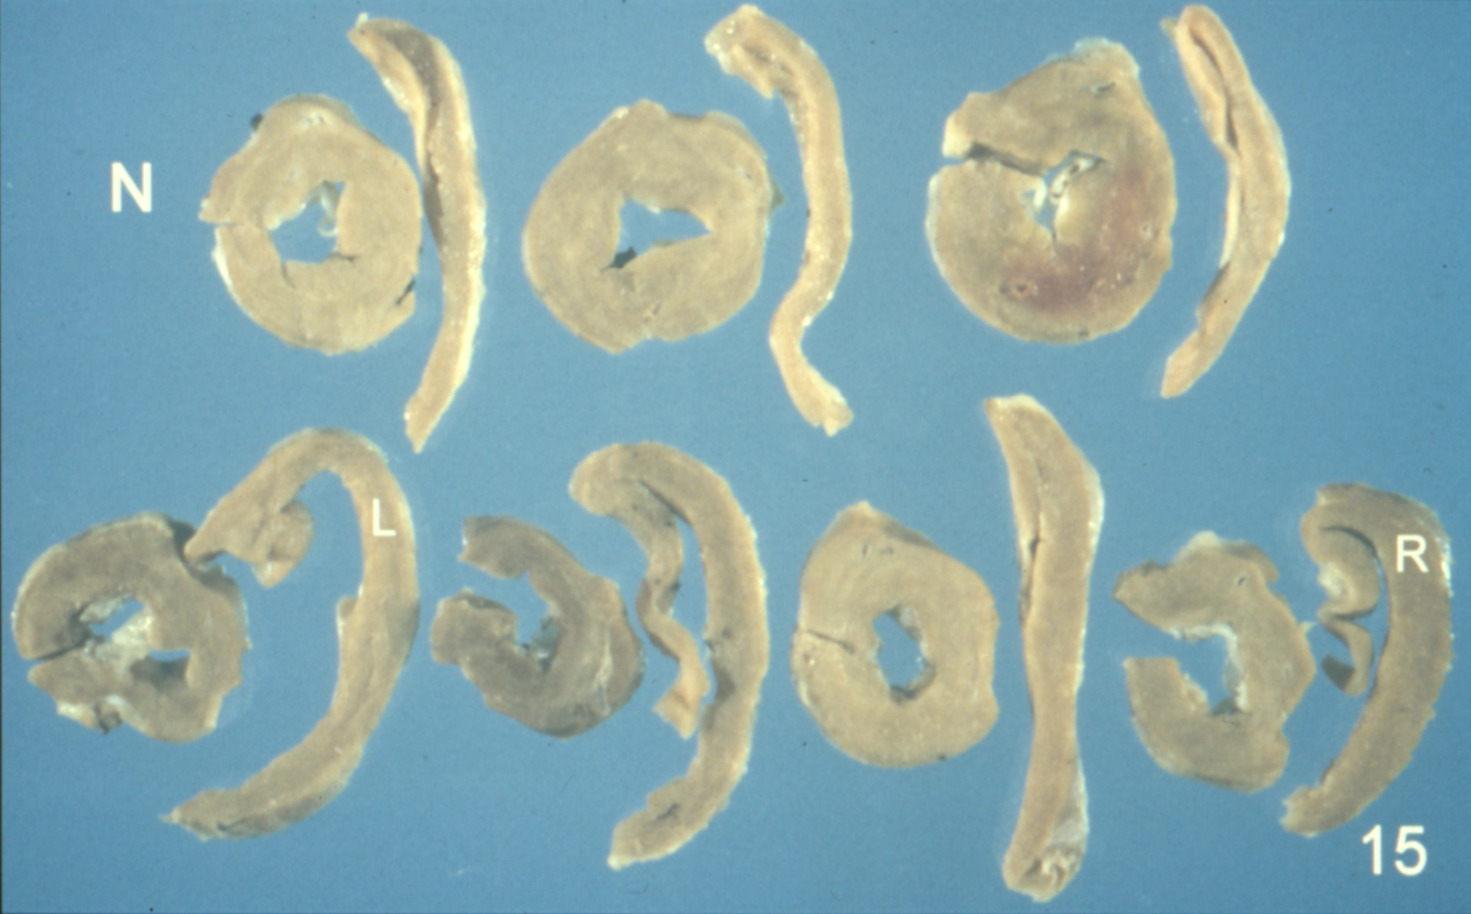

Ascites syndrome in meat-type chickens (slide study set no. 23)

Chickens--Diseases Ascites

Slide Study Set #23, Ascites Syndrome in Meat-Type Chickens (includes 27 color slides), 2001